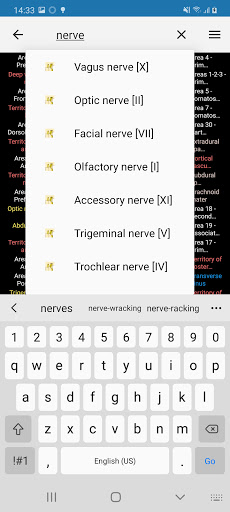

- Mudah menemukan struktur anatomi berkat pencarian indeks

e-Anatomy memiliki lebih dari 26.000 gambar yang berisi serangkaian gambar dalam tampilan aksial, koronal, dan sagital serta radiografi, angiografi, gambar diseksi, bagan anatomi, dan ilustrasi. Semua gambar medis diberi label dengan cermat, lebih dari 967.000 label tersedia dalam 12 bahasa termasuk Terminologia Anatomica Latin.